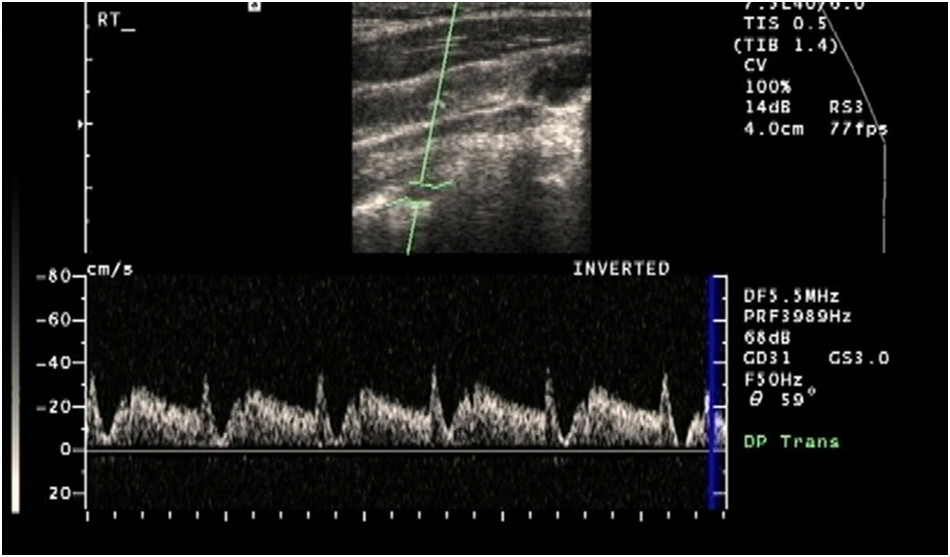

Pacjent zgłosił się do poradni chirurga naczyniowego z powodu okresowo występujących zaburzeń równowagi oraz objawów chromania ręki lewej podczas wykonywania prac fizycznych. W badaniu przedmiotowym stwierdzono wyczuwanie tętna na obu tętnicach promieniowych. Różnica ciśnienia skurczowego mierzonego na obu kończynach górnych wynosiła 10 mm Hg. Pacjenta skierowano na badanie dupleksowe tętnic szyjnych i kręgowych. Oceniając tętnicę kręgową po stronie lewej stwierdzono obecność przepływu ze spektrum przedstawionym na poniższej rycinie. Charakter przepływu nie podlegał zmianie na całej długości ocenianej tętnicy. Prawdopodobnym rozpoznaniem jest:

Pytanie 104

W celu potwierdzenia rozpoznania wstępnego postawionego w pytaniu nr 103 należy przeprowadzić weryfikację w postaci: